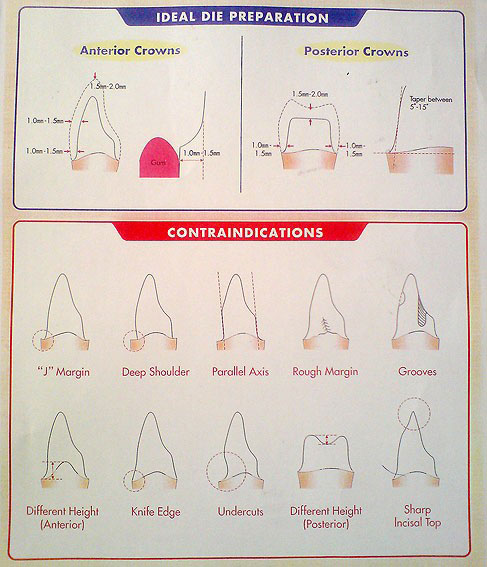

میزان تراش